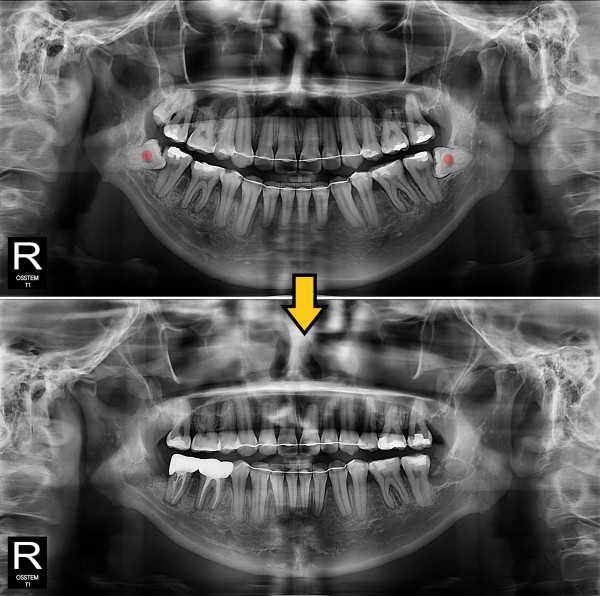

사랑니발치 부분 매복 사랑니

826e40416d712e6cd444a78bde93df4b_1767858465_8678.jpg